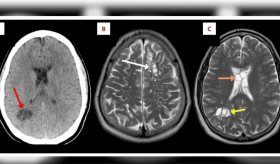

El paciente que visitaba una clínica por migrañas, tenía larvas parasitarias creciendo en su cerebro y terminó con un diagnóstico de neurocisticercosis.